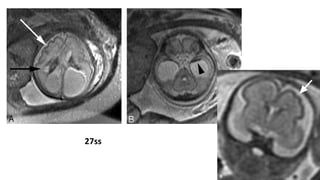

27

ss

TRASNTORNOS DE MIGRACIÓN: LISENCEFALIA Lissencephaly, typeI is characterized by agyria with or without pachygyria, a wide cortical mantle and minimal or no hydrocephalus. Four layer cortex. · Miller-Dieker syndrome (17p13 deletion) has lissencephaly combined with dysmorphic facial features and other possible associated anomalies. · Norman-Roberts syndrome · Isolated type I lissencephaly Lissencephaly, type II. Vascular bundles and fibroglial tissue are present in the cortex and subarachnoid space. Lissencephaly, type II typically has hydrocephalus and additional serious central nervous system defects. It is usually part of a syndrome. · HARD+/-E syndrome, an acronym for Hydrocephalus, Agyri, Retinal dysplasia, Encephalocele (Walker-Warburg syndrome) · COMS (Cerebro-oculomuscular syndrome) · Other subtypes of type II lissencephaly are possible Lissencephaly is found in Neu-Laxova syndrome, lethal autosomal recessively inherited disorder consisting of growth retardation, microcephaly, lissencephaly, corpus callosum agenesis, intracranial calcifications, cerebellar hypoplasia, facial dysmorphism, microophthalmia, exophthalmus, cataracts, absent eyelids, hydrops, ichthyosis, contractures of extremities and syndactyly.

27 ss • Malformación severade corteza cerebral, que resulta de falla en migración neuronal durante el 3° y 4° mes de gestación. • Clínica: Retraso psicomotor severo Retraso del desarrollo Convulsiones Retraso en crecimiento • Este defecto acarrea un mal pronóstico del RN, con RM y alta tasa de recurrencia, si está ligado a defectos genéticos.